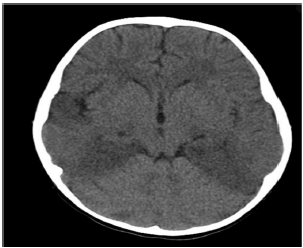

Ao exame neurológico, agitado, Glasgow 14, sem déficits focais, mas com discurso desconexo. Realizada TC de crânio: